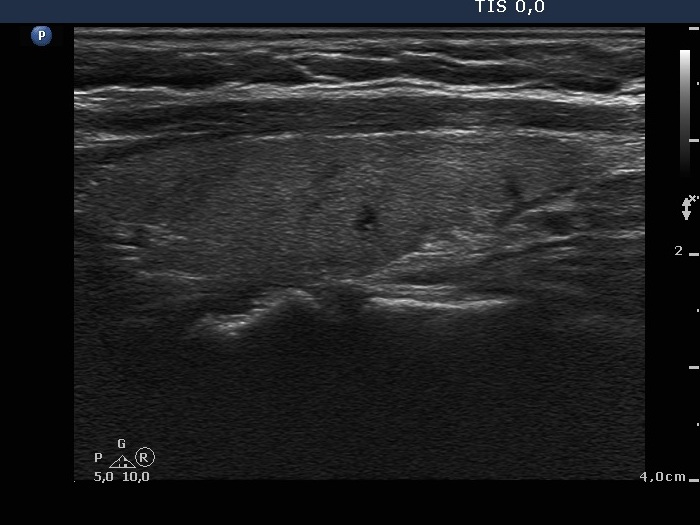

Subacute granulomatous de Quervain's thyroiditis - Case 12.

4 months (ultrasonographic picture 5)

Left lobe, longitudinal view. There are several small insignificant lesions within the lobe.